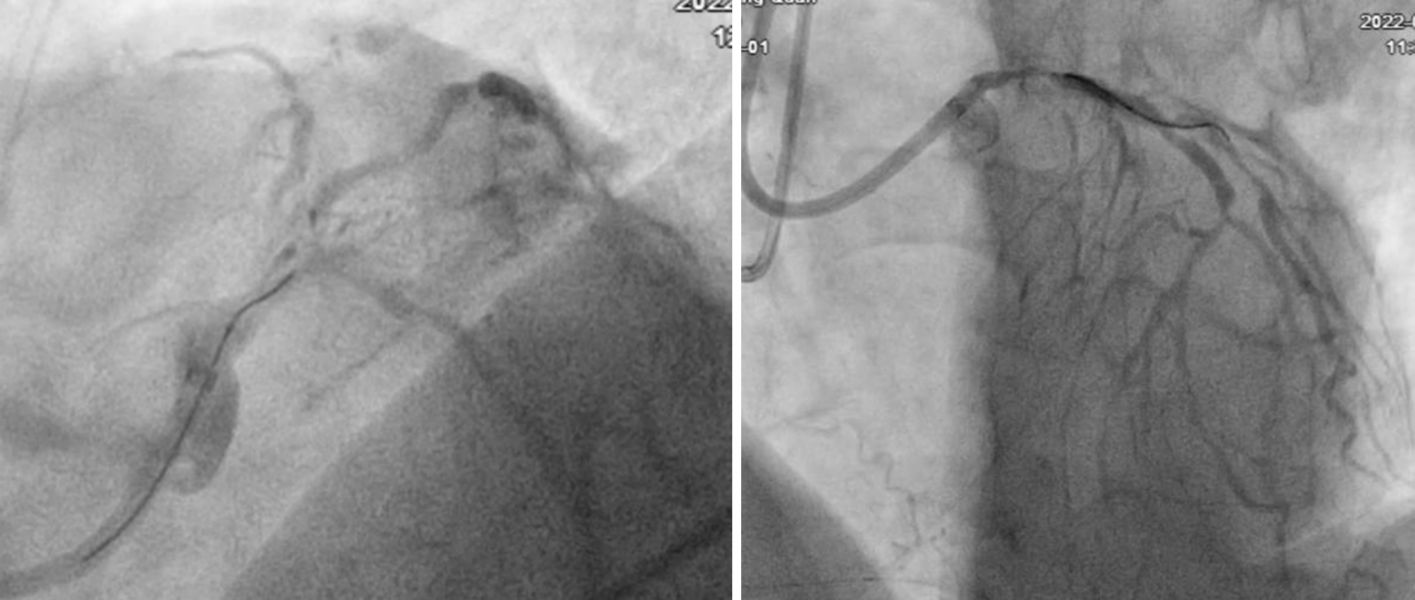

心内一科介入团队在为该患者进行冠脉介入治疗 5月13日,心内一科介入团队首先为患者植入主动脉球囊反搏,然后顺利开通前降支慢性闭塞病变,血管内超声检查后先后使用1.25mm、1.75mm旋磨头对左主干及前降支的钙化病变进行旋磨,并顺利地植入支架,手术总耗时3小时余。术后患者恢复良好,胸闷症状消失,目前已出院。

心内一科介入团队在为该患者进行冠脉介入治疗